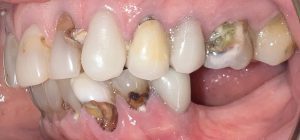

Patient with missing teeth and full mouth of infection & decay seeking help of a biological dentist

The patient presented to Virginia Biological Dentistry for a comprehensive biological evaluation after experiencing extensive dental breakdown and ongoing infection. Examination revealed advanced decay in the upper dentition, missing teeth, and widespread infection affecting all remaining lower teeth, rendering the lower teeth non-salvageable.

Cavities and Infections and broken teeth